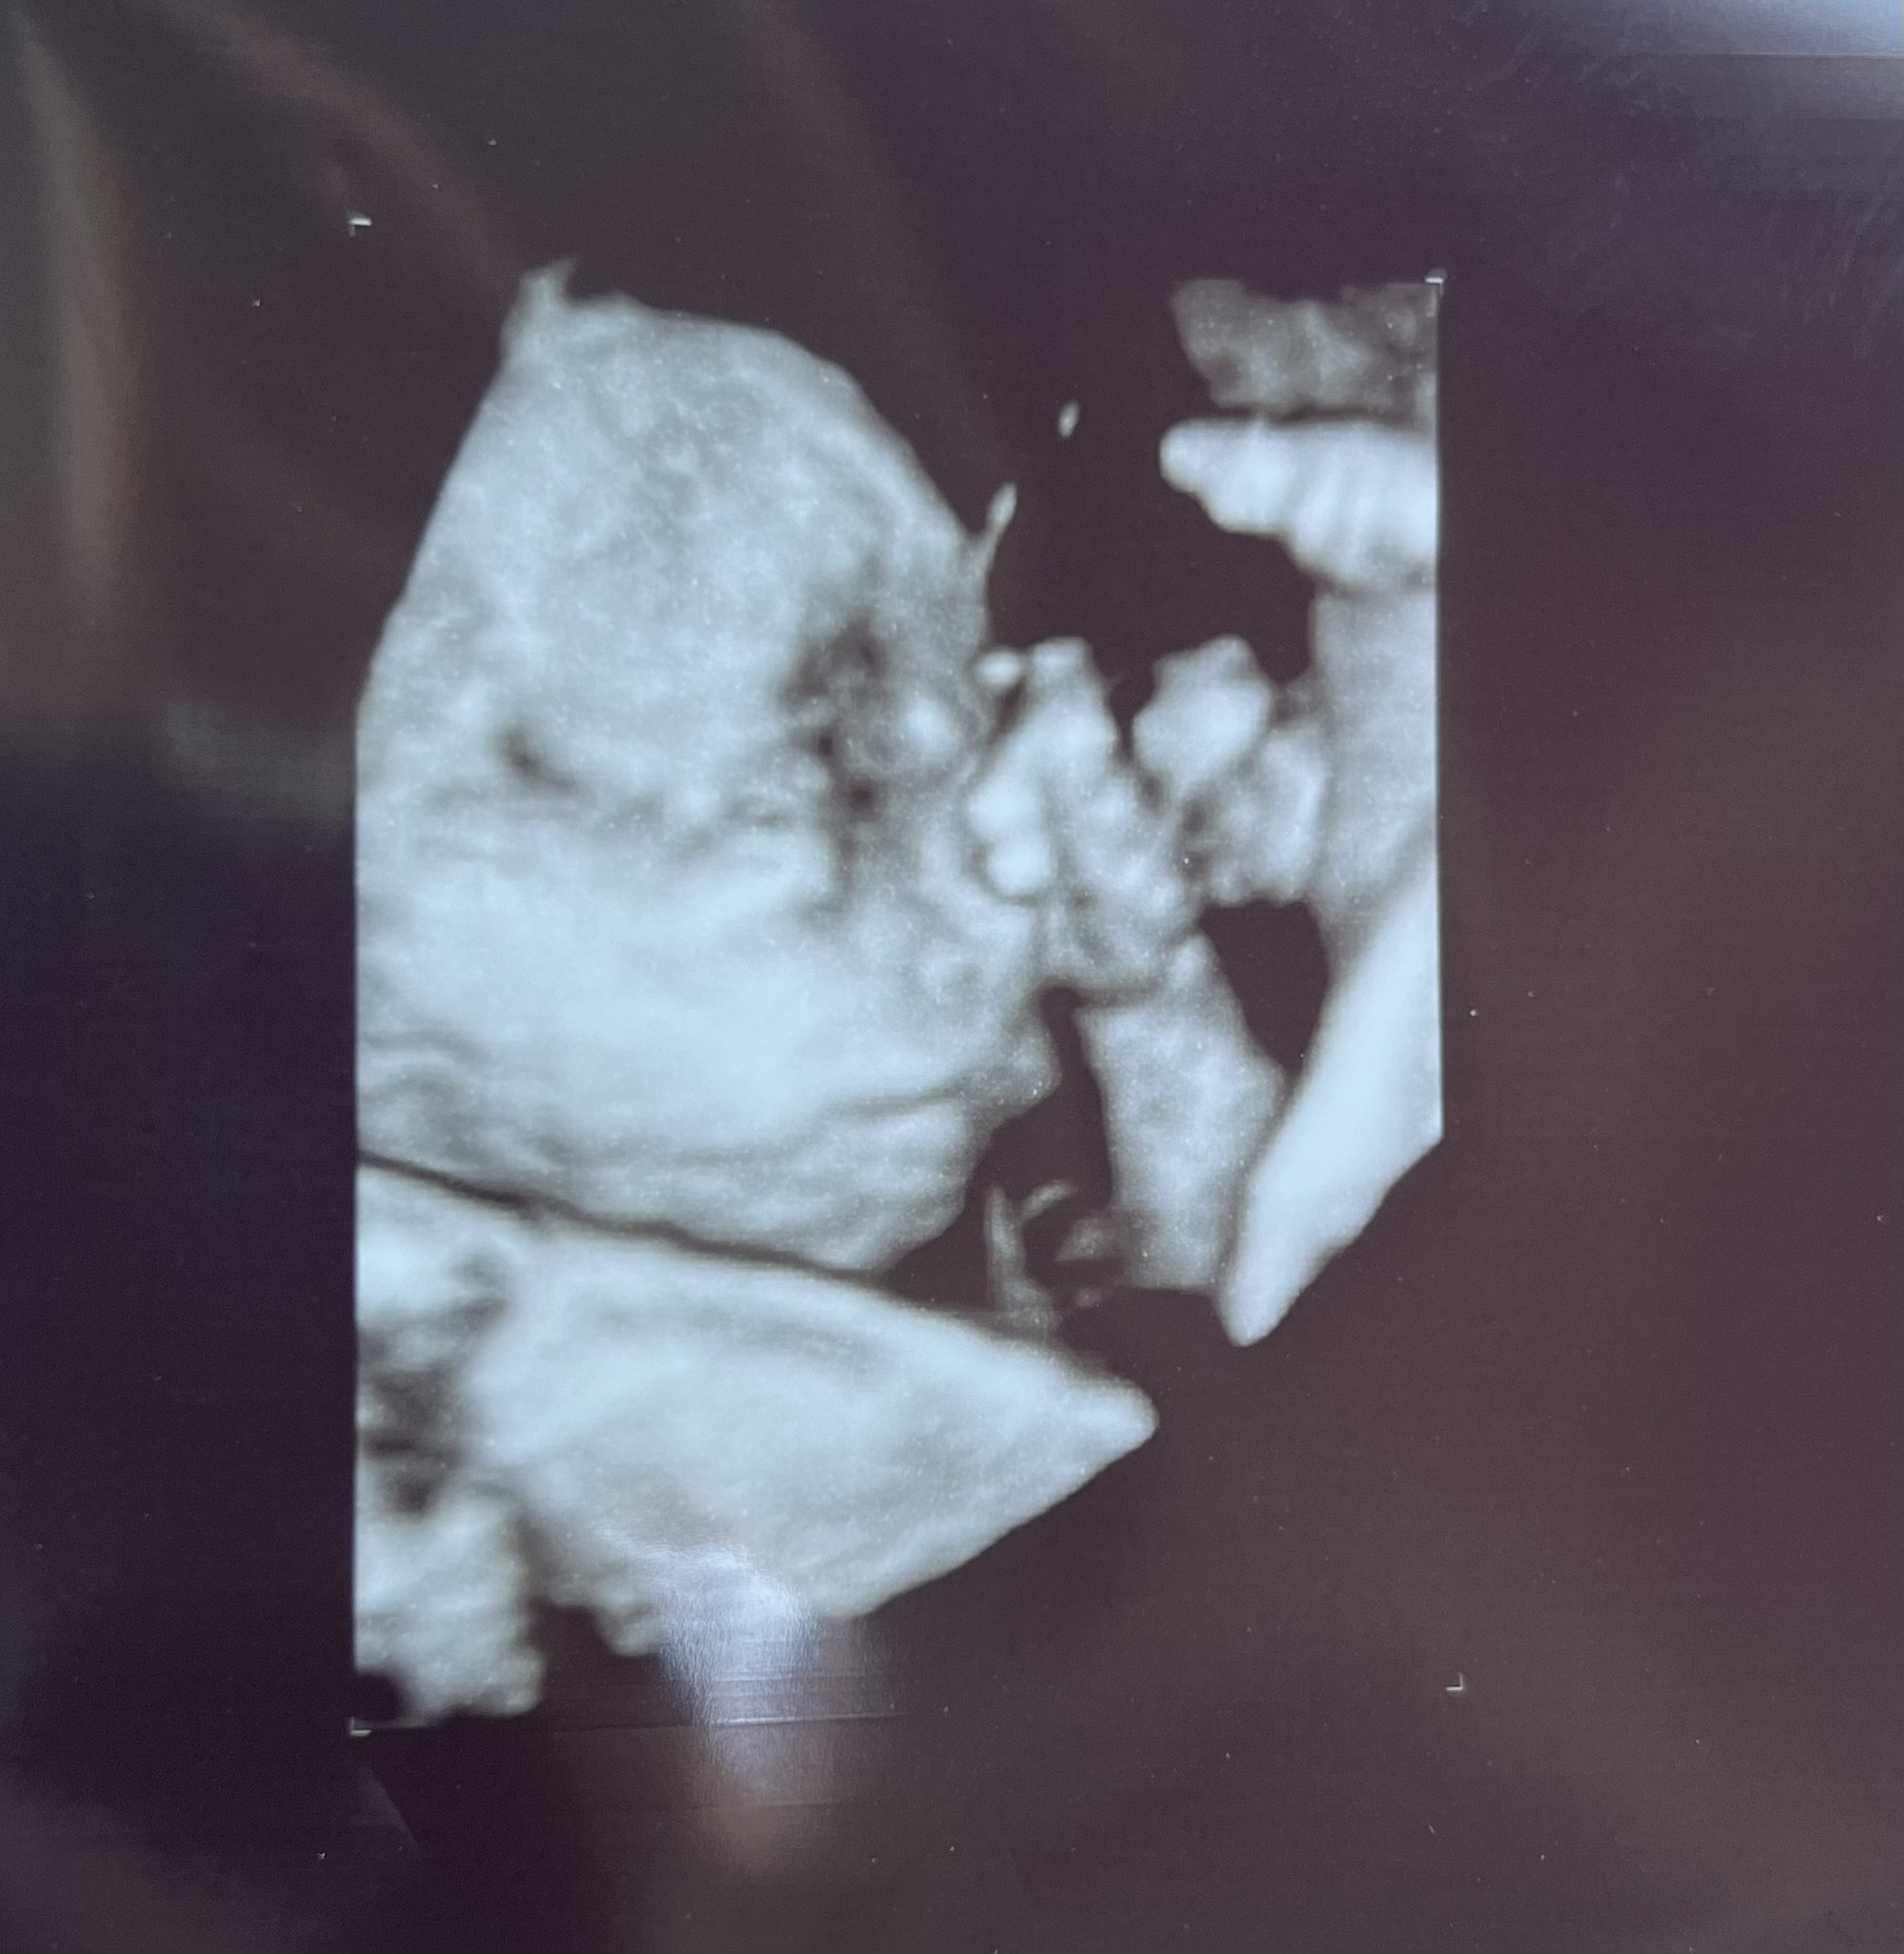

AmMcc12

member

June 2023

Nugget at 23+4. We didn’t get 3D with my first so this is awesome!

Me: 26 DH: 25

DS1 -- 9/30/2016